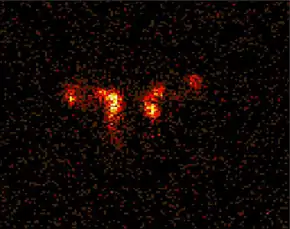

Dacryoscintigraphy (DSG), also known as lacrimal scintigraphy, is a nuclear medicine technique for imaging the lacrimal apparatus. It is used to identify obstructions, for example in the lacrimal duct, nasal cavity or nasolacrimal duct.

The typical procedure involves use of Technetium-99m colloid, or in some cases pertechnetate. The colloid is prepared with an activity of approximately 20 megabecquerels in 1 millilitre (ml). Patients place their head in a support and chin rest and a single drop of 0.01 ml is delivered to each eye. Imaging with a gamma camera commences immediately, with a number of images acquired over 15 minutes.[1][2]